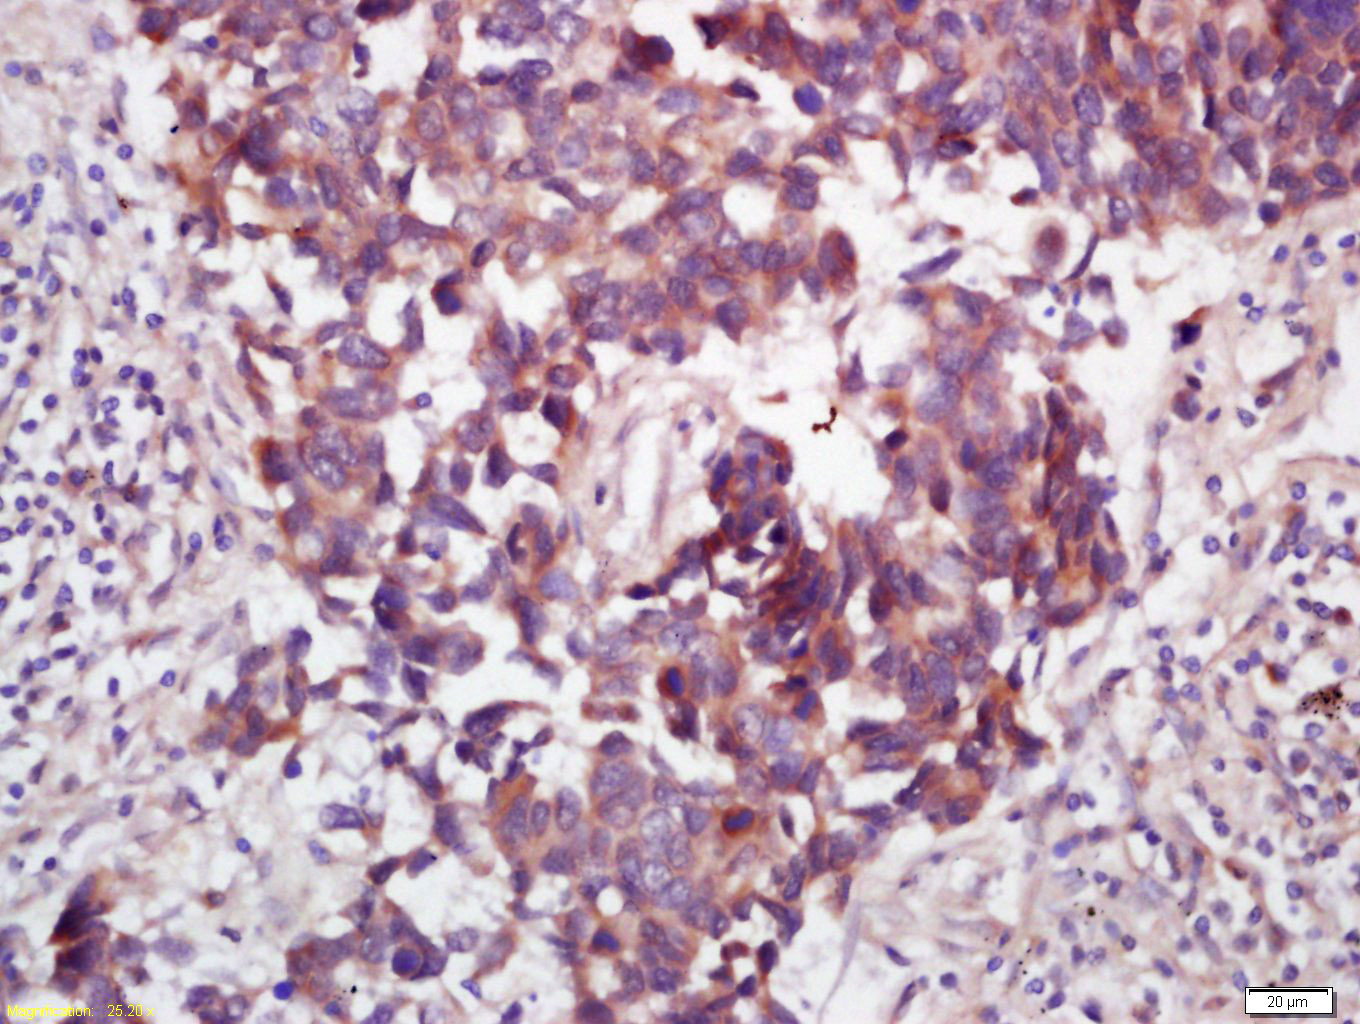

Paraformaldehyde-fixed, paraffin embedded (mouse uterus); Antigen retrieval by boiling in sodium citrate buffer (pH6.0) for 15min; Block endogenous peroxidase by 3% hydrogen peroxide for 20 minutes; Blocking buffer (normal goat serum) at 37°C for 30min; Antibody incubation with (WNT7B) Polyclonal Antibody, Unconjugated (bs-6244R) at 1:200 overnight at 4°C, followed by operating according to SP Kit(Rabbit) (sp-0023) instructionsand DAB staining.

Paraformaldehyde-fixed, paraffin embedded (Human kidney); Antigen retrieval by boiling in sodium citrate buffer (pH6.0) for 15min; Block endogenous peroxidase by 3% hydrogen peroxide for 20 minutes; Blocking buffer (normal goat serum) at 37°C for 30min; Antibody incubation with (WNT7B) Polyclonal Antibody, Unconjugated (bs-6244R) at 1:200 overnight at 4°C, followed by operating according to SP Kit(Rabbit) (sp-0023) instructionsand DAB staining.

Tissue/cell: human lung carcinoma; 4% Paraformaldehyde-fixed and paraffin-embedded; Antigen retrieval: citrate buffer ( 0.01M, pH 6.0 ), Boiling bathing for 15min; Block endogenous peroxidase by 3% Hydrogen peroxide for 30min; Blocking buffer (normal goat serum,C-0005) at 37℃ for 20 min; Incubation: Anti-WNT7B Polyclonal Antibody, Unconjugated(bs-6244R) 1:200, overnight at 4°C, followed by conjugation to the secondary antibody(SP-0023) and DAB(C-0010) staining

Tissue/cell: rat brain tissue; 4% Paraformaldehyde-fixed and paraffin-embedded; Antigen retrieval: citrate buffer ( 0.01M, pH 6.0 ), Boiling bathing for 15min; Block endogenous peroxidase by 3% Hydrogen peroxide for 30min; Blocking buffer (normal goat serum,C-0005) at 37℃ for 20 min; Incubation: Anti-WNT7B Polyclonal Antibody, Unconjugated(bs-6244R) 1:200, overnight at 4°C, followed by conjugation to the secondary antibody(SP-0023) and DAB(C-0010) staining